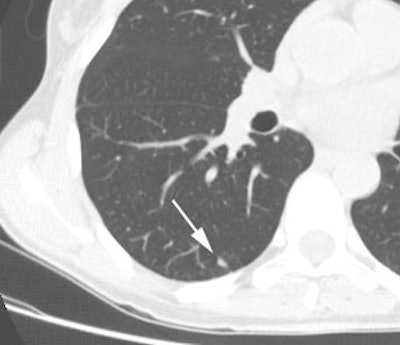

Small nodule: The patient shown below presented for evaluation of an 8 mm right lower lobe pulmonary nodule (white arrow). The PET scan was negative, but because of the lesions small size, the lack of uptake is not definitive for a benign lesion. Follow-up CT imaging will be required to document that the lesion remains stable over time. |